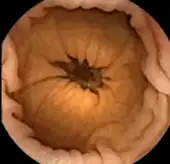

Medical uses

Esophagogastroduodenoscopy (EGD), employs a camera attached to a long flexible tube to view the upper portion of the gastrointestinal tract, namely the esophagus, the stomach, and the beginning of the first part of the small intestine called the duodenum. A colonoscope, inserted through the rectum, can view the colon and the distal portion of the small intestine, the terminal ileum. These two types of endoscopy however cannot visualize the majority of the middle portion of the small intestine.

Capsule endoscopy is therefore used to examine parts of the gastrointestinal tract that cannot be seen by standard endoscopy. It is useful when the disease is suspected in the small intestine, and can sometimes be used to find the site of gastrointestinal bleeding or the cause of unexplained abdominal pain, such as Crohn's disease. However, unlike EGD or colonoscopy, it cannot be used to treat pathology that may be discovered. Common reasons for using capsule endoscopy include diagnosis of unexplained bleeding, iron deficiency, or abdominal pain, searching for polyps, ulcers, and tumors of the small intestine, and diagnosis of inflammatory bowel disease.[10]